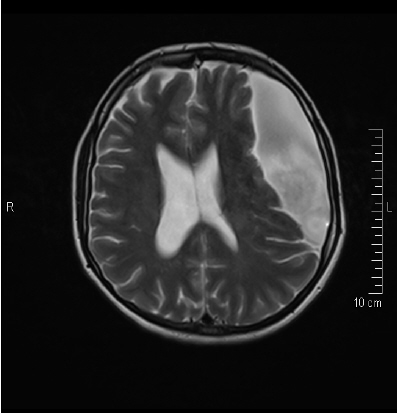

Hatte ja gesagt dass ich heute MRT Termin habe. Ich denke ich stell einfach mal von jeder Perspektiven Serie ein Bild ein und dann könnt ihr Euch selbst eine Meinung bilden ob gut oder schlecht. Einfach auf das Bild klicken, dann seht ihr es etwas größer.

Ich denke es ist nicht so ganz zu übersehen welches hier der schlechte Teil ist in meinem Kopf ist und das meine Hirnmittellinie alles andere als gerade ist. Und dass sich die ganze Sache im Vergleich zu letztem Mal auch noch mal wieder ein Stückchen mehr breit gemacht hat in meinem Kopf brauch ich wohl auch nicht so ganz zu erwähnen.